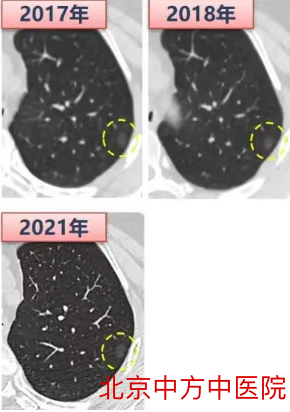

这个策略在多发GGO的病人中尤其适用,我们需要用长时间的随访,来确认到底哪些GGO是需要干预的,以及需要优先干预的,哪些是不用牺牲肺组织去切掉的GGO。正如下面这个病人(图三)。在2017年首次发现GGO的时候是右肺下叶的一个小GGO,此后随访在2018年发现左肺上叶有一个新的GGO,定期随访发现,右肺下叶初发的GGO并没有明显变化,而左肺上叶后出现的GGO反而从4mm增长到9mm。经过这5年的随访,证实左肺GGO恶性程度比右肺更高,所以制定的手术决策是胸腔镜左肺上叶楔形切除,术后病理提示是微浸润腺癌,右肺GGO因为没有变化可以继续随访。

图三多发GGO长期随访评估GGO危险度,进行最优手术决策